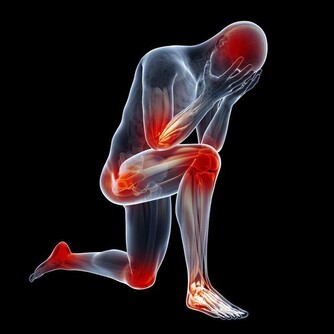

7、水使造血系統運轉正常,有助於預防某些類型癌症,特別是白血症和淋巴瘤。